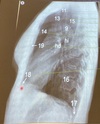

Q

•Paciente en posición recta

• Lado afectado sobre el registro

•Brazos levantados por encima de la cabeza

• Mentón hacia arriba

Posición lateral verdadera

* Rayo Central; perpendicular, dirigido a región

torácica media a nivel de 17

(8-10cms por debajo de la escotadura yugular)

¿Que proyección se desea obtener?

A

Proyección lateral